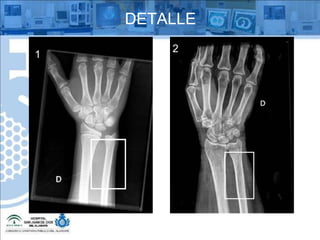

¿QUÉ ES  ? Detalle Radiológico Es la capacidad de apreciar las pequeñas estructuras  en la radiografía

DETALLE Tenemos que distinguir tres conceptos: Nitidez del detalle Visibilidad Borrosidad

DETALLE NITIDEZ Es la habilidad de un sistema para reproducir y resaltar los más mínimos detalles anatómicos del sujeto. Se refiere a los bordes, si se ven claros hay buena nitidez y viceversa.

DETALLE VISIBILIDAD Se refiere a la capacidad para ver el detalle, si se aprecian bien las pequeñas estructuras hay buena visibilidad y viceversa.

DETALLE BORROSIDAD Es la reproducción defectuosa de trazos o bordes que aparecen desvanecidos y confusos. La nitidez y la borrosidad son por tanto términos antagónicos.

DETALLE 1 2